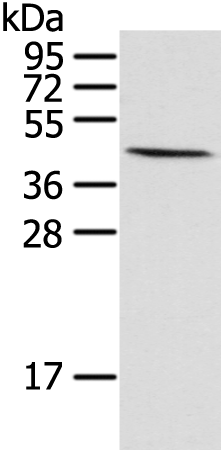

WB Predicted band size: |

40 kDa |

WB Positive control: |

Human fetal muscle tissue |

WB Recommended dilution: |

200-1000 |